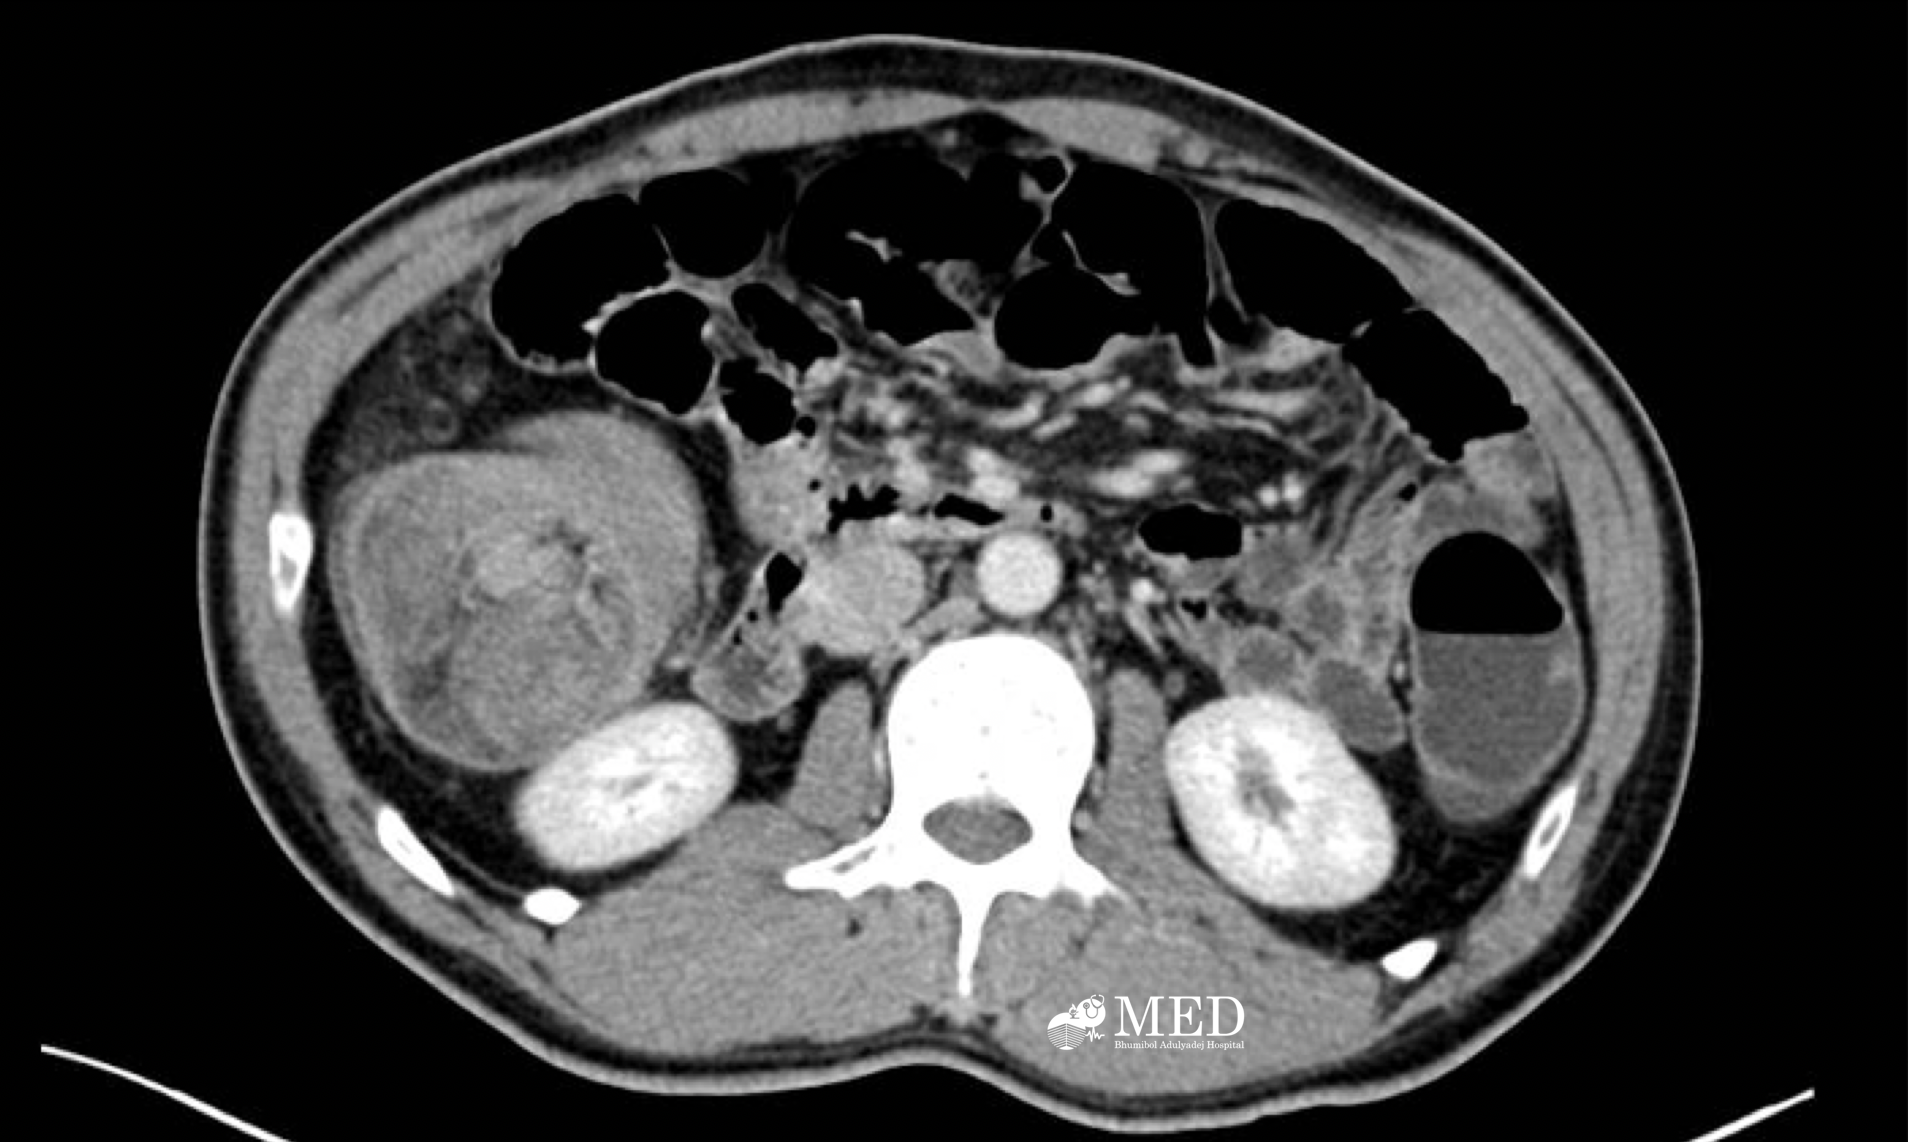

103. A 41-year-old man with abdominal pain and significant weight loss.

Case male 41 years old, no known underlying disease, presented with abdominal pain for 7 weeks and significant weight loss 4 kg in 2 months.

Question:  Please describe the film and give the diagnosis.